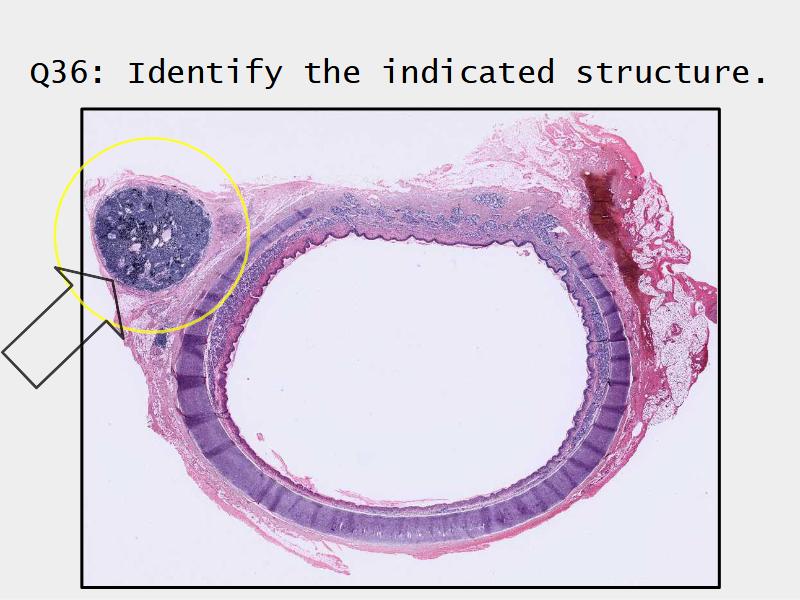

Trachea

Respiratory epithelium

- Pseudostratified

- Ciliated

- Columnar

- Epithelium with

- 4 Cells

- Ciliated columnar cells

- Non-ciliated columnar cells

- Goblet cells

- Basal cells